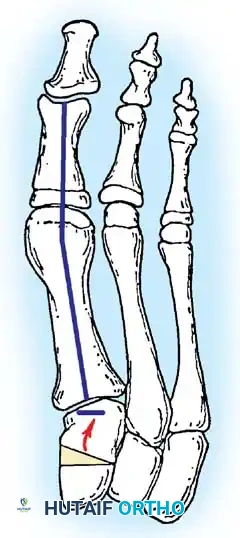

Inadequate vascularity or sensibility should be investigated thoroughly before bunion surgery is considered. In addition, the position of the articular surface of the metatarsal head in relation to the longitudinal axis of the fi rst metatarsal should be determined (Fig. 78-8). Standard preoperative radiographs should include standing dorsoplantar and lateral views, a nonstanding lateral oblique view, and axial sesamoid views (Fig. 78-9). The hallux valgus angle and the fi rst-second intermetatarsal angle should fi rst be drawn on the standing dorsoplantar view by bisecting the shafts of the bones (Fig. 78-10), with an awareness of the normal ranges. These angles are most frequently cited as guidelines for treatment decisions, but Donnelly et al. reported that interobserver measurements of the hallux valgus angle varied by approximately 6 degrees and of the intermetatarsal angle by 4 degrees. They cautioned that potential errors in measurement should be considered when these parameters are used to make treatment decisions. The hallux valgus interphalangeus angle and any evidence of degenerative arthritic changes at the fi rst metatarsophalangeal or metatarsocuneiform joints should be documented. Oddities may be present and, if overlooked, may compromise a technically well-done procedure. Mann emphasized that the presence of an os inter-

Fig. 78-8 A, Determination of position of articular surface of metatarsal head in relation to longitudinal axis of fi rst metatarsal. B, Measurement of distal metatarsal articular angle at time of surgery. Markings are at medial and lateral margins of articular surface of fi rst metatarsal head and longitudinal axis of fi rst metatarsal shaft. metatarseum between the bases of the fi rst and second metatarsals might preclude the effectiveness of a soft-tissue procedure alone to provide suffi cient correction of the increased intermetatarsal angle. Likewise, accessory sesamoids and prominent ungual tuberosities at the interphalangeal joint contribute to a painful callus at the tibial side of this joint. An os tibialis externum frequently is associated with excessive hallux valgus interphalangeus. Varus of the fi rst metatarsal might be a signifi cant part of the overall deformity of the foot even with an intermetatarsal angle of less than 10 degrees. Metatarsus varus with a relatively small hallux valgus angle (15 to 20 degrees) may produce signifi cant deformity even though the angles are not excessive. The usefulness of computer-assisted compared with manual measurement of the intermetatarsal angle, hallux valgus angle, and distal metatarsal articular angle is still uncertain. Both methods have closer interobserver and intraobserver correlation in measurement of the intermetatarsal angle and hallux valgus angle than in measurement of the distal metatarsal articular angle. The reliability of either method has such a wide range (5 degrees), however, that measurements of these angles, although useful as a guide, do not provide a completely reliable indication of the magnitude of deformity. Condon et al. suggested that the reliability of the intermetatarsal angle can be improved by careful technique and by making the measurements at least twice and averaging them. Schneider et al. reported two methods of determining angular measurements based on distinctly different reference points: (1) a longitudinal axis of the fi rst metatarsal using middiaphyseal reference points, and (2) a center-head technique using a center head (center of the articular surface) and center base

(center of the proximal diaphysis) as reference points. They found that measured correction of the hallux valgus and intermetatarsal angles varied by approximately 9 degrees depending on which reference points were used. Recommendations of Coughlin, Saltzman, and Nunley (American Orthopaedic Foot and Ankle Society Ad Hoc Committee on Angular Measurements) included standardized radiographic technique, specifi c placement of reference points (Fig. 78-11), use of a protractor rather than a goniometer for measurements, and, after distal osteotomies, dual measurements using a center-head technique and a Mose sphere.

Fig. 78-10 Method of measuring hallux valgus angle and intermetatarsal angle. Center points are connected, and intersecting lines defi ne angles.

Fig. 78-11 Location of reference points for fi rst and second metatarsals are between 1 and 2 cm from distal articular surface and proximal articular surface of each metatarsal. Because of shorter length of hallux, reference points are placed between 0.5 and 1 cm from proximal and distal articular surface of proximal phalanx. (From Coughlin MJ, Saltzman CL, Nunley JA II: Angular measurements in the evaluation of hallux valgus deformities: a report of the ad hoc committee of the American Orthopaedic Foot and Ankle Society on angular measurements, Foot Ankle Int 23:68, 2002.) support and the medial capsule acting as a spring on stretch. Osteotomy usually is indicated in patients with this medial wedged opening of the joint. If a fi rm forefoot wrap reduces the intermetatarsal angle to a normal value and decreases the hallux valgus angle, however, while congruously rotating the base of the fi rst metatarsal on the medial cuneiform without levering the joint open medially, the McBride procedure can correct the deformity. Correction is improved by excision of the fi bular (lateral) sesamoid because the adductor hallucis and lateral head of the fl exor hallucis brevis are released, markedly reducing the valgus moment at the fi rst metatarsophalangeal joint. In addition, the pull of the fi bular sesamoid on the fl exor hallucis longus through its tendon sheath and pulley system is prevented, reducing another important valgus-producing force on the hallux at the metatarsophalangeal joint. If the fi bular sesamoid is excised, the medial capsule should be repaired with the hallux held in 10 to 15 degrees of valgus. This position must be maintained by a postoperative dressing for 3 or 4 weeks.